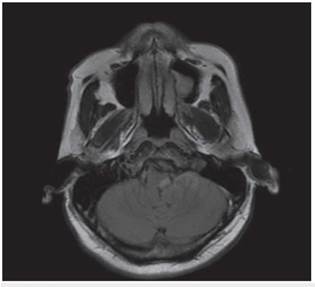

<p>Los estudios de hemograma, nitrógeno ureico, creatinina, glucemia y electrolitos se encontraron dentro de los rangos normales, el perfil lipídico mostró: colesterol total 160 mg/dl, colesterol HDL 50 mg/dl, colesterol LDL 89,8 mg/dl, triglicéridos 101 mg/dl. La tomografia de cráneo simple no mostró sangrado ni signos de isquemia. Se realizó una resonancia magnética cerebral simple que permitió evidenciar en las secuencias de T2 y FLAIR <italic>(Fluid Attenuation Inversion Recovery)</italic> una zona de hiperintensidad de señal a nivel del bulbo raquídeo en la región dorso-lateral caudal izquierda que es hipointensa en T1 (<xref ref-type="fig" rid="f1">figuras 1</xref>,<xref ref-type="fig" rid="f2">2</xref>,<xref ref-type="fig" rid="f3">3</xref>,<xref ref-type="fig" rid="f4">4</xref>). En la secuencia de difusión se observa restricción de la misma en la zona descrita con fenómeno de pseudonormalización al igual que en el mapa ADC <italic>(Apparent Coefficient Diffusion}</italic> (<xref ref-type="fig" rid="f5">figuras 5</xref>,<xref ref-type="fig" rid="f6">6</xref>). Los anteriores hallazgos se interpretaron como compatibles con un infarto bulbar lateral izquierdo.</p>

<p>El paciente se caracterizó por tener principalmente dis-fagia, disfonía, vértigo, ataxia y hemiparesia ipsilateral, las cuales rápidamente mejoraron, siendo llamativo la ausencia de nistagmo el cual se reporta en una incidencia importante. El estudio por resonancia magnética se logró realizar 1 semana posterior al inicio de los síntomas, lo cual generó la limitante de observar pseudo-normalización en la secuencia DWI (Diffusion Weighted Imaging) y por ende ausencia de una clara restricción de la difusión. En el T2 corte coronal se puede ver extensión hacia zonas caudales de la unión bul-bomedular, lo cual explicaría por qué presentó compromiso del tracto cortico-espinal siendo la primera causa, la lesión de las fibras ya decusadas provenientes del hemisferio contrala-teral ya sea por isquemia o por efecto de masa por el edema adyacente, este hallazgo se correlaciona con lo mayormente reportado en otras publicaciones. Un elemento importante en el paciente fue el inicio súbito de los síntomas posterior a realizar una rotación brusca del cuello con dolor cervical asociado, lo cual debe ubicar al clínico en un contexto cuya principal etiología a estudiar sea la disección cervical dada además la ausencia de factores de riesgo cardiovasculares y la edad cercana a los 50 años, sin embargo, en una angiografía convencional tomada 3 semanas después, no se evidenció esta etiología según lo informado por radiología. A pesar del compromiso motor, no todos los pacientes que cursan con síndrome de Opalski tienen una afectación marcada de la funcionalidad e independencia <xref ref-type="bibr" rid="B17"><sup>17</sup></xref> y la debilidad evidenciada es leve y transitoria permitiendo su recuperación hasta el 100 % previo, como se observó en este caso. Por otro lado, es importante evitar complicaciones tempranas como la broncoaspiración y neumonitis secundaria y, por ende, se hace imperativo plantear desde el ingreso de estos pacientes una vía alterna de alimentación a través de sonda naso u orogástrica o gastrostomía mientras se lleva a cabo el proceso de rehabilitación de la disfagia de forma paralela.</p>